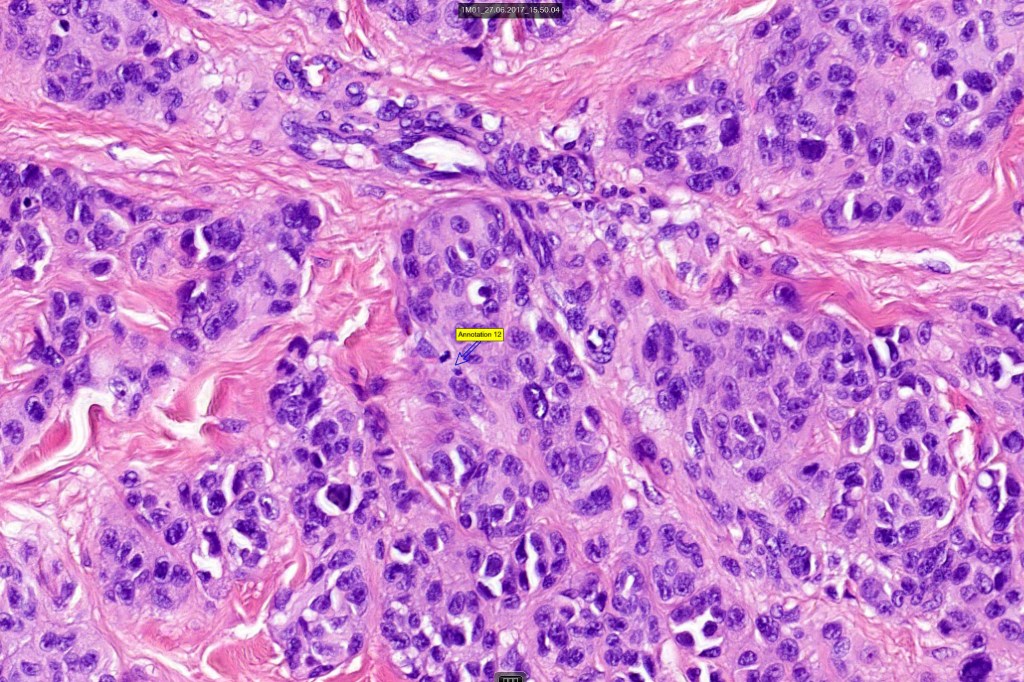

Histological features

•Verrucous or dome-shaped, at low power, the lesion looks like a nevus

•Expansile nodules or diffuse

•Compression of connective tissue

•Mimics type-A cells, (lesions which mimic type B nevus cells are often classified as small cell melanoma, this is important as the differential diagnosis is very different- see separate blog)

•Subtle or not so subtle impaired maturation with depth (sometimes this is evident at scanning magnification)

•Subtle nucleolar prominence

•Subtle pleomorphism

•Mitoses invariable including often in the deep aspect